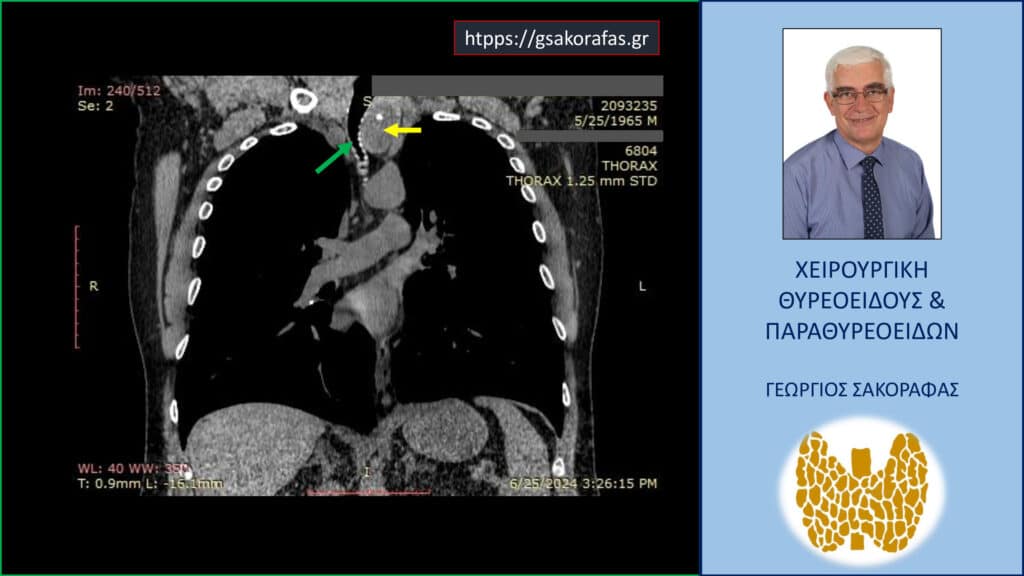

- Γιατί είμαστε σε θέση να εκτελέσουμε με ασφάλεια και αποτελεσματικότητα κάθε είδους χειρουργική επέμβαση θυρεοειδούς – παραθυρεοειδών, ακόμη και σε επιπλεγμένα (δύσκολα) περιστατικά, όπως εκτεταμένοι λεμφαδενικοί καθαρισμοί σε καρκίνο θυρεοειδούς, επεμβάσεις σε λίαν ευμεγέθεις καταδυόμενες στο μεσοθωράκιο βρογχοκήλες, υποτροπές παθήσεων θυρεοειδούς (συμπεριλαμβανομένου του καρκίνου θυρεοειδούς), υποτροπές υπερπαραθυρεοειδισμού, αδενώματα παραθυρεοειδών σε έκτοπη θέση ή λόγω υπεράριθμων παραθυρεοειδών, διάχυτη υπερπλασία παραθυρεοειδών, κλπ.